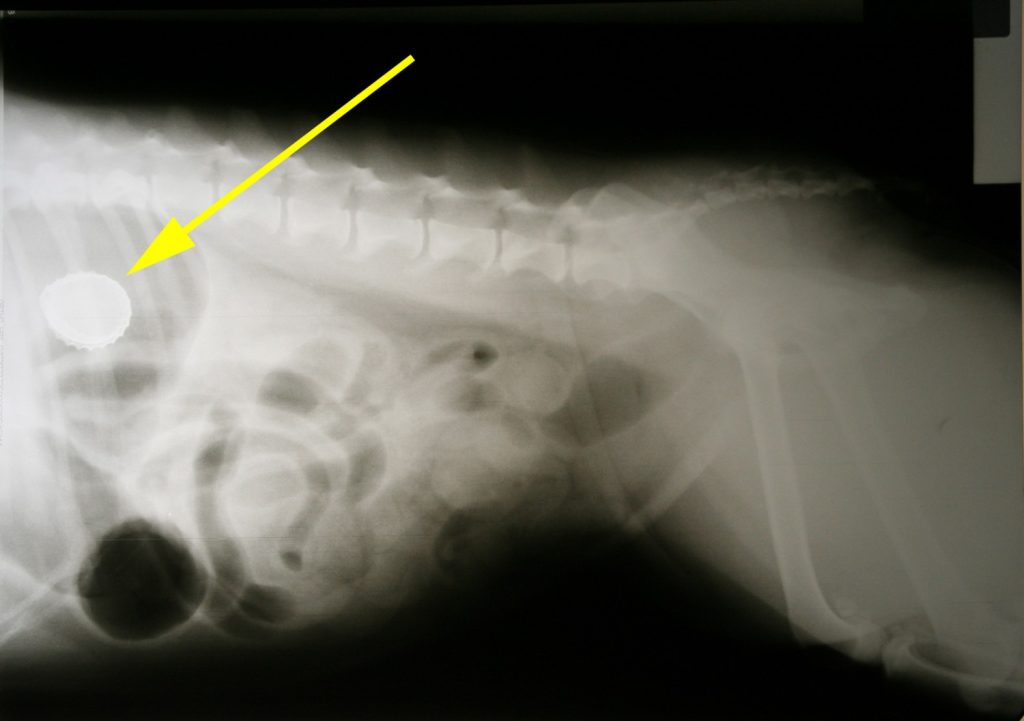

Bij het algemeen lichamelijk onderzoek viel met name op dat de temperatuur 40 graden was, de buik voorin een beetje gevoelig was en er iets bloed aan de thermometer zat. Het leek allemaal mee te vallen maar toch zat ze ons op de een of andere manier niet lekker. In overleg hebben we besloten een rontgenfoto te maken van de buik. Hierop zagen we al snel het probleem: in de maag zat een prachtig voorbeeld van een kroonkurk.

We besloten om dezelfde avond nog te gaan opereren (deze kroonkurk zat er waarschijnlijk al zeker een maand in, maar was blijkbaar pas sinds kort echt klachten gaan geven).